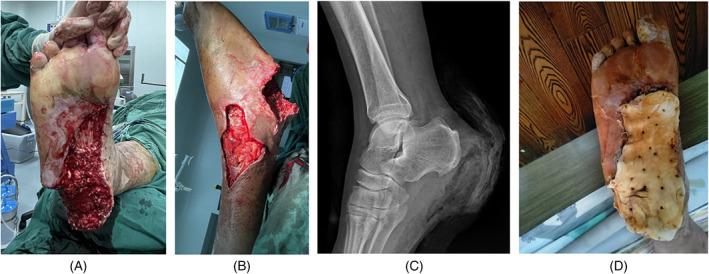

The treatment of traumatic wounds with exposed bone or tendons is often challenging. An induced membrane (IM) is used to reconstruct bone defects, as it provides an effective and sufficient blood supply for bone and soft-tissue reconstruction. This study explored a novel two-stage strategy for wound management, consisting of initial wound coverage with polymethyl methacrylate (PMMA) and an autologous split-thickness skin graft under the IM. Fifty inpatients were enrolled from December 2016 to December 2019. Each patient underwent reconstruction according to a two-stage process. In the first stage, the defect area was thoroughly debrided, and the freshly treated wound was then covered using PMMA cement. After 4-6 weeks, during the second stage, the PMMA cement was removed to reveal an IM covering the exposed bone and tendon. An autologous split-thickness skin graft was then performed. Haematoxylin and eosin (H&E) staining and immunohistochemical analysis of vascular endothelial growth factor (VEGF), CD31 and CD34 were used to evaluate the IM and compare it with the normal periosteal membrane (PM). The psychological status and the Lower Extremity Function Scale (LEFS) as well as any complications were recorded at follow-up. We found that all skin grafts survived and evidenced no necrosis or infection. H&E staining revealed vascularised tissue in the IM, and immunohistochemistry showed a larger number of VEGF-, CD31- and CD34-positive cells in the IM than in the normal PM. The duration of healing in the group was 5.40 ± 1.32 months with a mean number of debridement procedures of 1.92 ± 0.60. There were two patients with reulceration in the group. The self-rating anxiety scale scores ranged from 35 to 60 (mean 48.02 ± 8.12). Postoperatively, the LEFS score was 50.10 ± 9.77. Finally, our strategy for the management of a non-healing wound in the lower extremities, consisting of an IM in combination with skin grafting, was effective, especially in cases in which bony structures were exposed in the elderly. The morbidity rate was low.

外伤性骨或肌腱外露伤口的治疗往往具有挑战性。诱导膜(IM)用于重建骨缺损,因为它为骨和软组织重建提供了有效的充足的血液供应。本研究探讨了一种新的两阶段伤口管理策略,包括最初用聚甲基丙烯酸甲酯(PMMA)覆盖伤口,然后在 IM 下进行自体刃厚皮片移植。2016 年 12 月至 2019 年 12 月期间,50 名住院患者入组。每位患者均根据两阶段流程进行重建。在第一阶段,彻底清创缺损区域,然后用 PMMA 水泥覆盖新鲜处理的伤口。4-6 周后,在第二阶段,去除 PMMA 水泥,露出覆盖外露骨和肌腱的 IM。然后进行自体刃厚皮片移植。苏木精和伊红(H&E)染色以及血管内皮生长因子(VEGF)、CD31 和 CD34 的免疫组化分析用于评估 IM,并与正常骨膜(PM)进行比较。记录心理状态、下肢功能量表(LEFS)以及任何并发症。我们发现所有皮片均存活,无坏死或感染。H&E 染色显示 IM 中有血管化组织,免疫组化显示 IM 中 VEGF、CD31 和 CD34 阳性细胞数多于正常 PM。该组的愈合时间为 5.40±1.32 个月,平均清创次数为 1.92±0.60 次。该组有 2 例患者再溃疡。自评焦虑量表评分范围为 35 至 60 分(平均 48.02±8.12 分)。术后,LEFS 评分为 50.10±9.77。最后,我们采用 IM 联合皮片移植治疗下肢难愈性伤口的策略有效,尤其是在老年人存在骨结构外露的情况下。发病率较低。